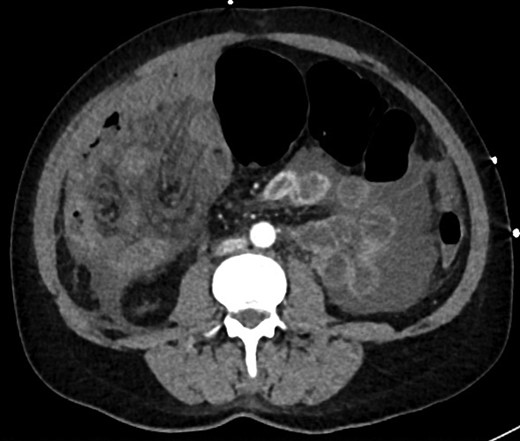

Colonoscopy revealed melanosis coli, diverticulosis and grade four hemorrhoids. She was admitted overnight following haemorrhoidectomy. The following morning she complained of abdominal pain, which she described similar to diverticulitis, and she was tender on exam. To rule out perforation, a plain film abdomen was performed. Findings were suggestive of gaseous distension following colonoscopic air insufflation without evidence of free gas (Fig. 1). Watchful waiting approach was adopted, however the patient deteriorated further during the course of the day. She had a vasovagal episode with tachycardia (134 bpm) and hypotension (67/47 mmHg). A venous blood gas revealed lactate level of 7 mmol/l. She underwent an urgent CT with findings suggestive of pericaecal internal hernia with the ileal loops located in the right paracolic gutter demonstrating features of ischemia (Fig. 2). There was moderate amount of free fluid, but no free gas to suggest perforation (Fig. 3). She was taken to theater that day for emergency laparotomy. The intraoperative findings included two litres of bloodstained fluid and floppy cecum with a band of adhesion to its own mesenteric base, probably adhesional having developed after the appendicectomy. This band has created a window through which three quarters of her small bowel had herniated and became strangulated. The bowel looked very ischemic, but not necrosed. The surgeons divided the adhesion, untwisted the small bowel and waited 20 minutes to allow sufficient time for bowel ischemia to recover. Fortunately, she did not require any bowel resection.

CT axial view showing dilated colon, internal hernia with ischemic small bowel loops, free fluid, but no free gas.